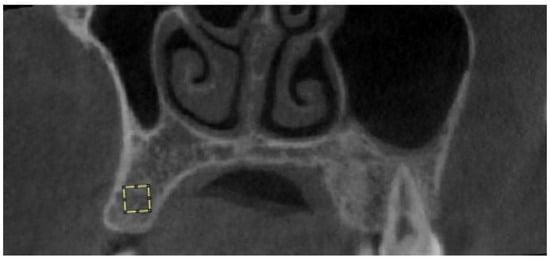

The obtained images were saved in JPEG format using Planmeca Romexis (version 3.8.3.R, Planmeca, Helsinki, Finland). Fractal analysis was performed using the box-counting method developed by White and Rudolph [22] in the ImageJ software version 1.53a (National Institutes of Health, Bethesda, MD, USA). All analyses were conducted by the same researcher (E.C.) on the same computer, using a 27-inch flat panel display with a resolution of 1920 × 1080 pixels (Samsung Electronics, Dublin, Ireland). The researcher was trained by İ.S., who has experience in fractal analysis. A 20 × 20 pixel region of interest (ROI) was selected avoiding roots, cortical bone, and vascular canals (Figure 1) [11]. JPEG images of the ROI were duplicated into two images, and a Gaussian filter (Sigma = 35 pixels) was applied to blur the images, for the purpose of eliminating fine- and medium-scale variations in image brightness. The blurred image was then subtracted from the original image. A value of 128 was added at each pixel location to discriminate bone marrow spaces from trabeculae. The resulting image was binarized into a two-color image, black and white, with a threshold value of 128. To reduce noise, the image was first eroded, then dilated. To make the trabeculae black and the marrow spaces white, the image was inverted. Finally, the image was skeletonized (Figure 2). The FD of the skeletonized image was calculated using the “Fractal Box Counting” option in the ImageJ software version 1.53a (National Institutes of Health, Bethesda, MD, USA).

Figure 1. Selection of 20 × 20 pixel ROI on a CBCT image.